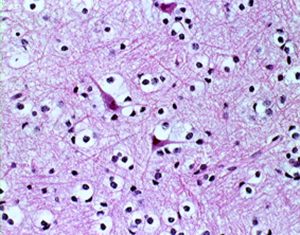

病理所見では,典型的な小さな円形核とその周囲が抜けてみえる perinuclear hallo (fried egg appearance)と細血管の chicken wire appearanceが見られます。

HE染色では,perinuclear haloをもった小型の腫瘍細胞が見られ,また右ではminigemistcyteと呼ばれる小さいけれどeoginophiricな胞体の豊かな腫瘍細胞の出現があり,典型的な乏突起膠腫の像です。

左に細かい石灰化が見られます。右は,グレード2の乏突起膠腫には珍しい血管内皮の増生 gromerulation なのですが,必ずしも悪性像とはいえません。通常の乏突起膠腫と同様にchicken wireと呼ばれるような細かい腫瘍血管網も存在しました。

病理像です。左側の部分はperinuclear hallowが多い典型的な乏突起膠腫です。右側の部分ではびまん性星細胞腫の像ですが,その中に乏突起膠腫に特徴的なchicken wireと呼ばれる細い血管網も見られます。乏突起星細胞腫と呼ばれるのですが、腫瘍性格は乏突起膠腫と同じもので,星細胞系腫瘍には入りません。1p/19q欠失があるもののIDH変異がないのでoligoastrocytoma, NOSです。